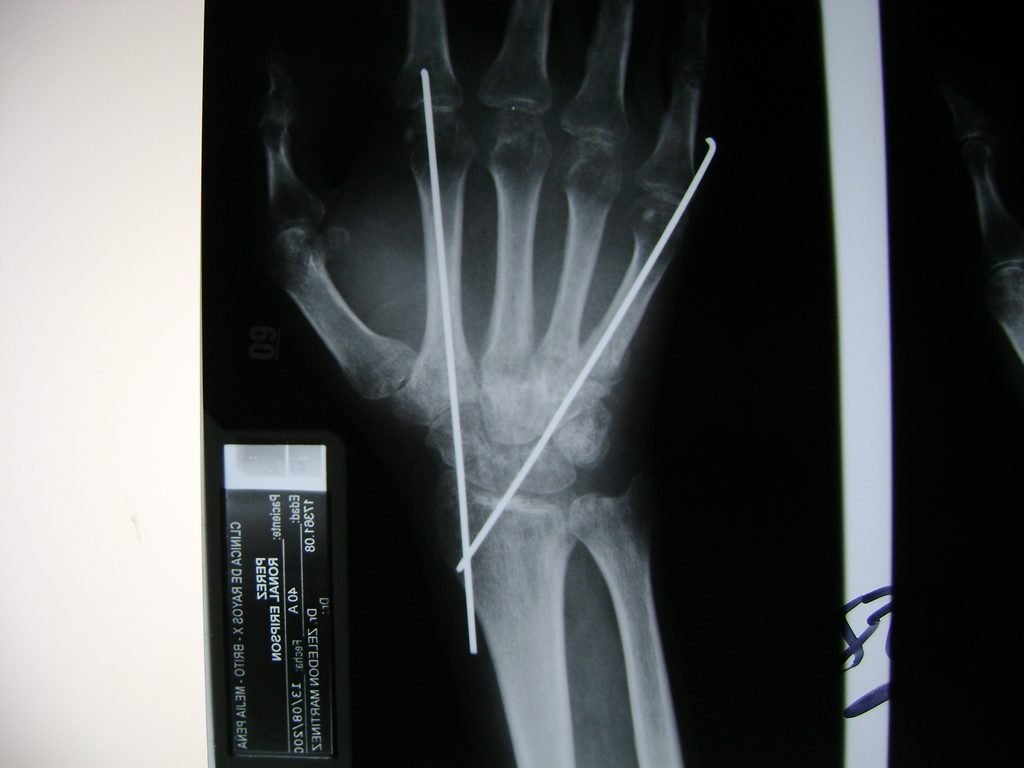

Cirugías de Codo - Cirugías de Muñecas y Manos

Los procedimientos más comunes en cirugía de la mano son aquellos destinados a reparar traumatismos, incluyendo lesiones de tendones, nervios, vasos sanguíneos, y articulaciones; huesos fracturados; y quemaduras, cortes, y otros daños de la piel.